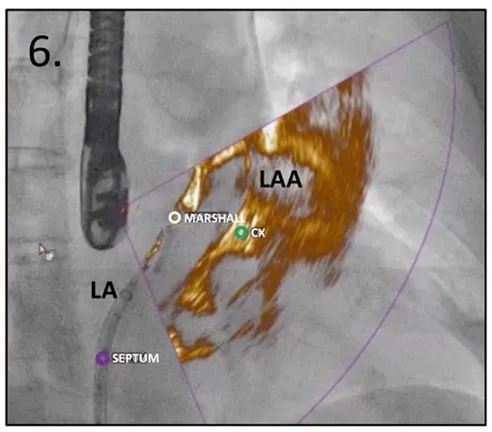

用猪尾导管和/或输送鞘进入左心耳

图6:在RAO投照和LAA叠加视图中,带有猪尾巴管的Mullins鞘在LAA内导航变得直观

缩写注释:Ao: 主动脉;CX,左回旋动脉;LA: 左心房;LAA: 左心耳;RA: 右心房;SP: 原发隔;SS: 继发隔;SVC: 上腔静脉;TEE: 经食管超声心动图;TSP: 经房间隔穿刺;白或黑色箭头,卵圆窝处的房间隔。